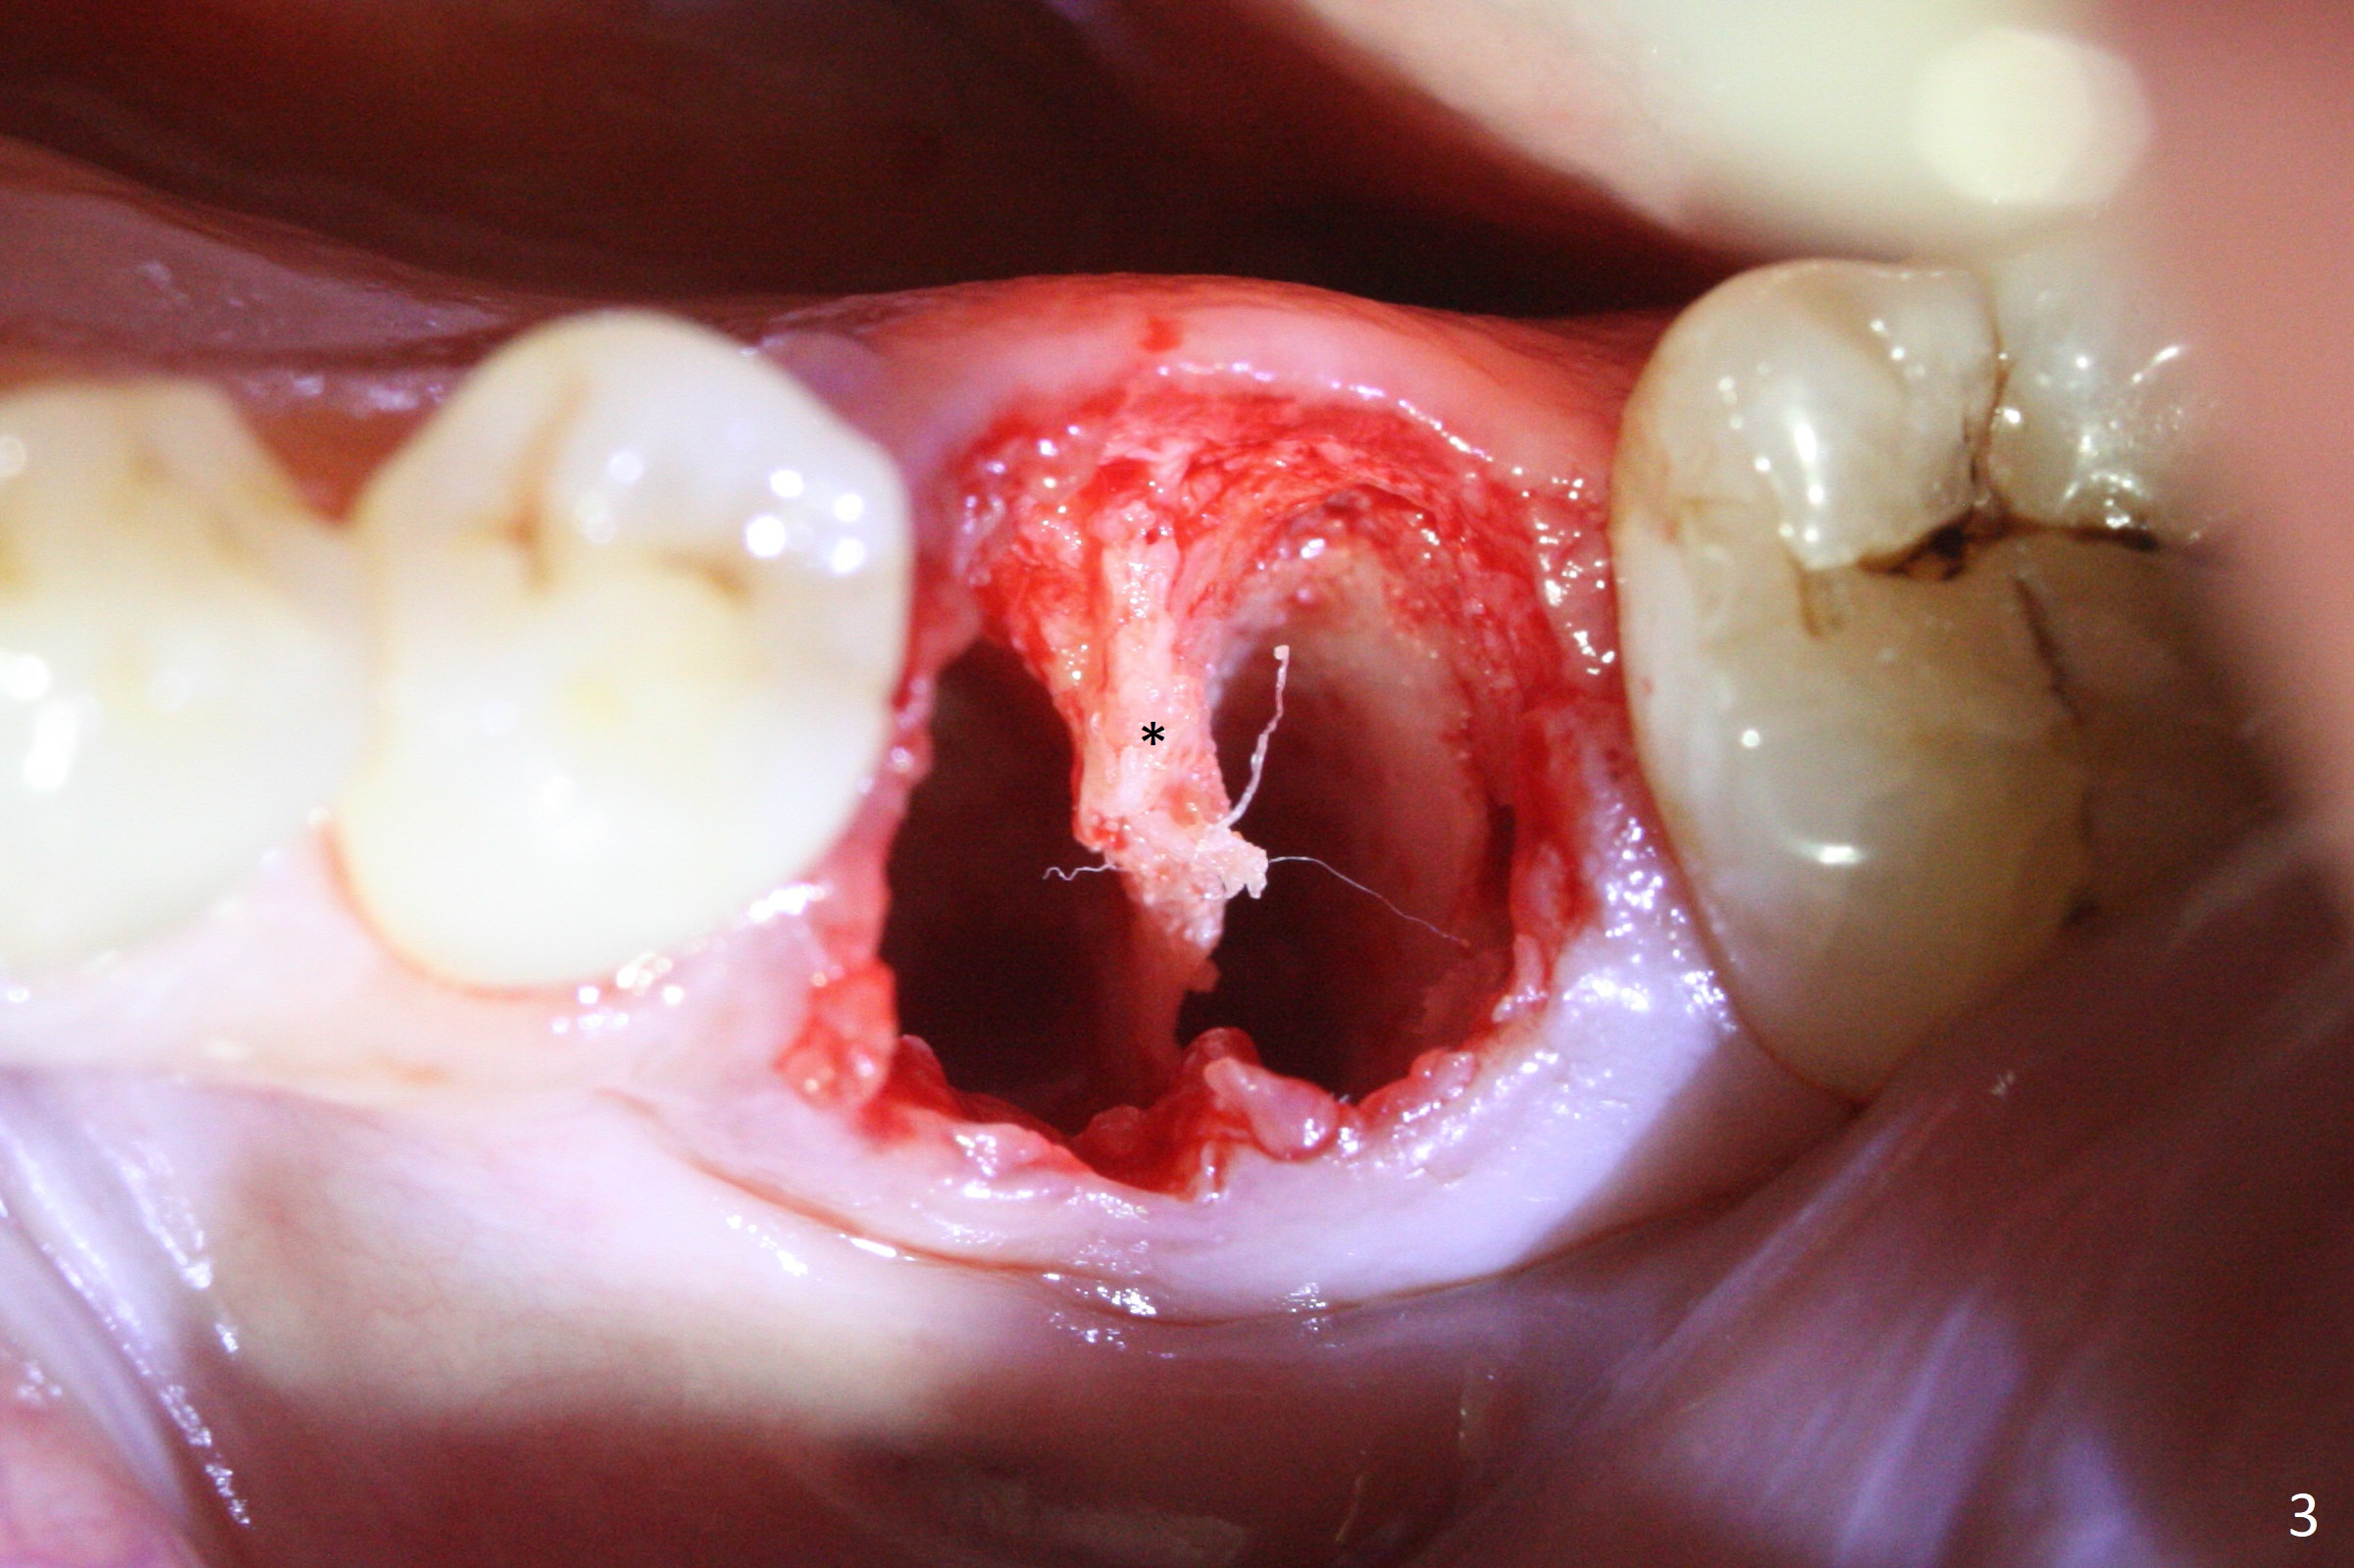

When the patient returns 9 months later, there is severe buccal gingival recession and abscess at #19 (Fig.1 *) with large mesial periradicular radiolucency (Fig.2 *).  The septum is thin and the buccal crest is low after extraction (Fig.3 * (mesial root vertical fracture)).  Osteotomy is initiated in the mesial socket immediately against the septum (Fig.4.5) with ~ 5 mm in the native bone.  Due to severe buccal plate resorption, a shorter implant is placed (Fig.6; 5x15 mm in stead of 18 mm).  There is at least 2 mm gap buccally for Vanilla Graft, which is also placed next to the implant and the neighboring root (Fig.7 *).  There is clearance from the Inferior Alveolar Canal (Fig.8 red dashed line).  Both the mesial and distal sockets heal 5.5 months postop (Fig.9), although the apical portion of the distal socket was not filled with allograft (Fig.7).  The implant was placed mesial.  The straight abutment (6.5x4(4) mm) (Fig.10) is changed to an angled one (5.5 x15 degrees 3 mm cuff (Fig.11)) before impression.  The implant is also placed buccally.  Therefore the implant position is far more important than its length.  The abutment is retightened 2.5 months post cementation, which is related to mesiobuccal placement of the implant (Fig.12).  An ideal trajectory is determined by drawing 2 horizontal lines (at crestal and apical levels: red lines in Fig.13), finding a central point of each line (vertical short line) and joining these 2 central points (Fig.14 pink line).  In fact the ideal osteotomy should have been established distal to the septum in this case.  Guided surgery may alleviate the issue.  The crown is not loose, but the patient feels that the implant tooth cannot sustain mastication.  In fact the screw is removed with hand driver (not wrench).  The abutment hex is rounded and worn.  A new 5.5x4(4) mm abutment is placed (without knowledge of previous use of an angled abutment) with mesial reduction to reduce undercut and buccodistal margin lowered to reduce gingival embrasure. It is that the straight abutment could decrease the chance of screw loosening.  Otherwise the implant has to be removed for better trajectory.